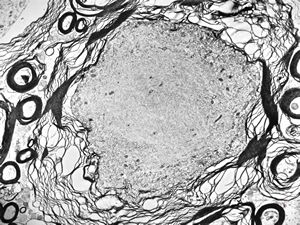

M,15y. | neurinoma fasc. optici